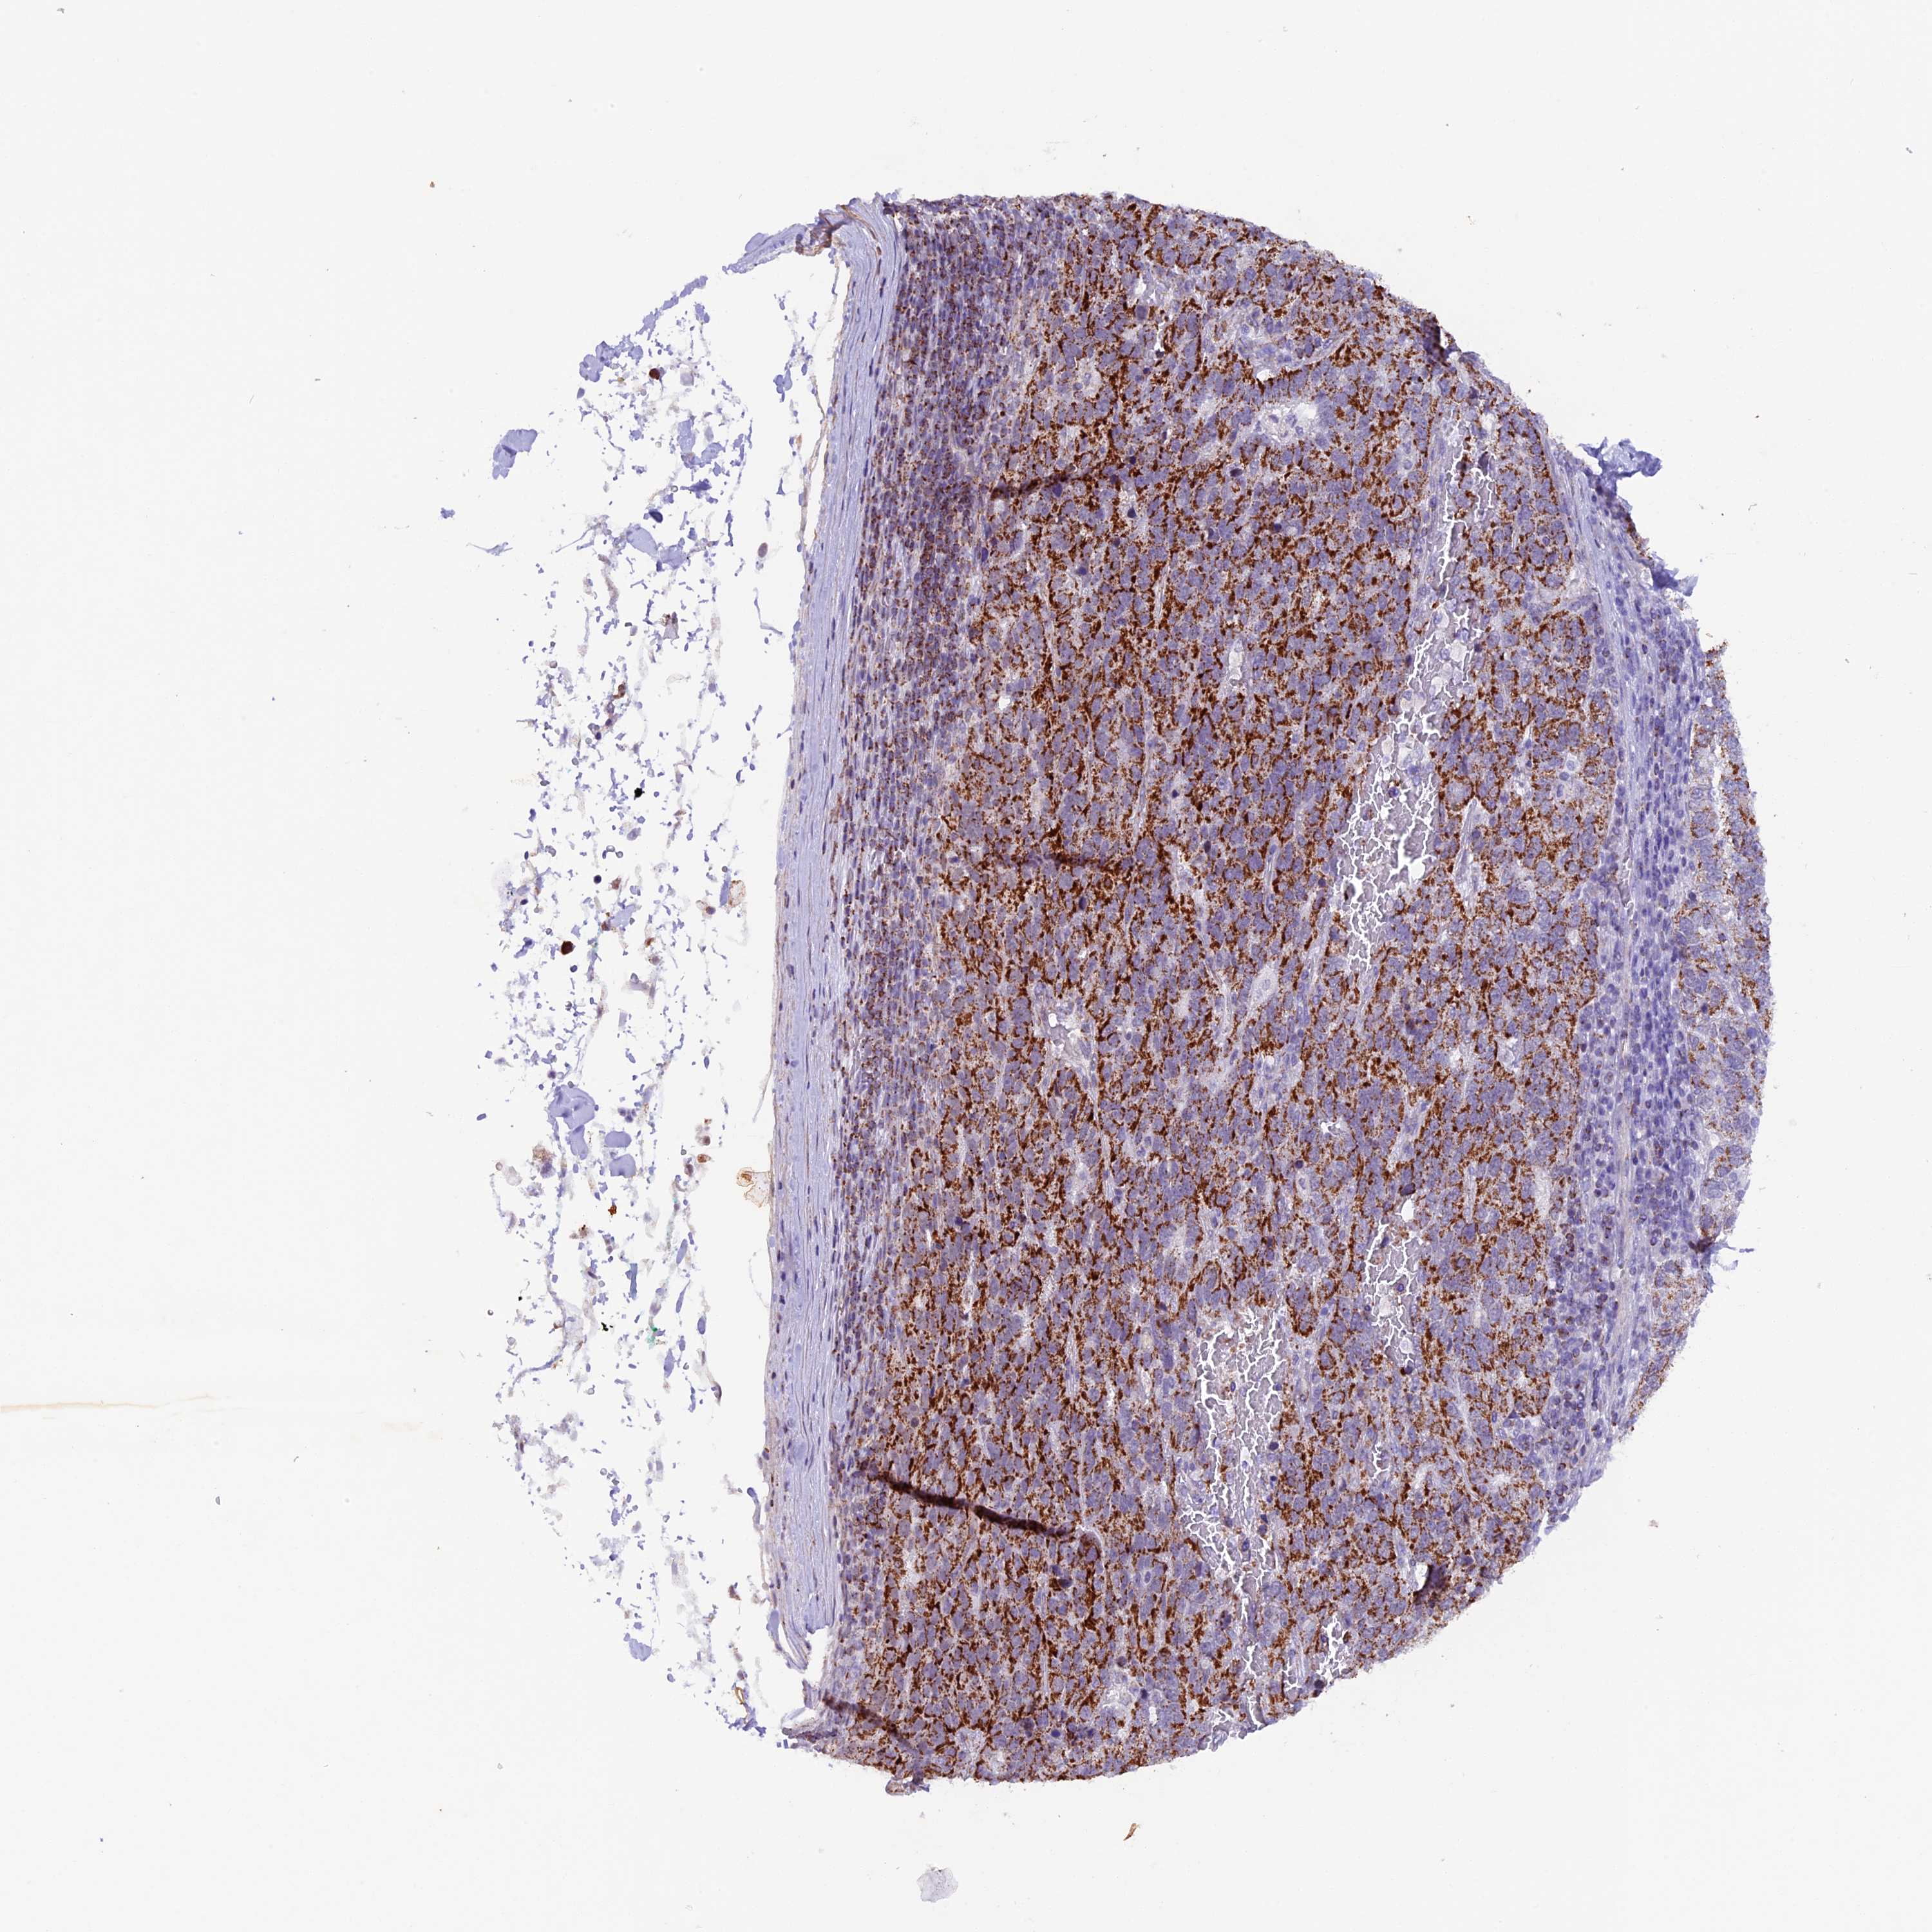

PANCREATIC CANCER - Protein expressioni

A mouse-over function shows sample information and annotation data. Click on an image to view it in a full screen mode. Samples can be filtered based on level of antibody staining by selecting one or several of the following categories: high, medium, low and not detected. The assay and annotation is described here.

Antibody stainingi

Antibody staining in the annotated cell types in the current human tissue is reported as not detected, low, medium, or high, based on conventional immunohistochemistry profiling in selected tissues. This score is based on the combination of the staining intensity and fraction of stained cells.

Each image is clickable and will lead to virtual microscopy that enables deeper exploration of all samples and also displays staining intensity scores, fraction scores and subcellular localization as well as patient and tissue information for each sample.

Antibody HPA040648

Staining

High

Medium

Low

Not detected

Intensity

Strong

Moderate

Weak

Negative

Quantity

>75%

75%-25%

<25%

None

Location

Nuclear

Cytoplasmic/membranous

Cytoplasmic/membranous,nuclear

Adenocarcinoma, NOS